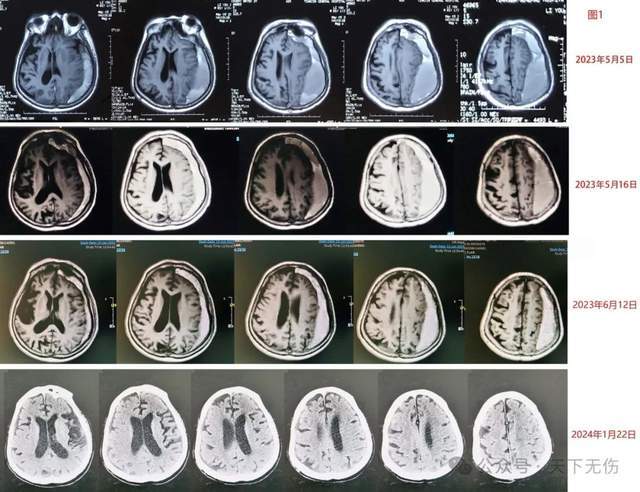

春節(jié)前最后一個門診暖人心